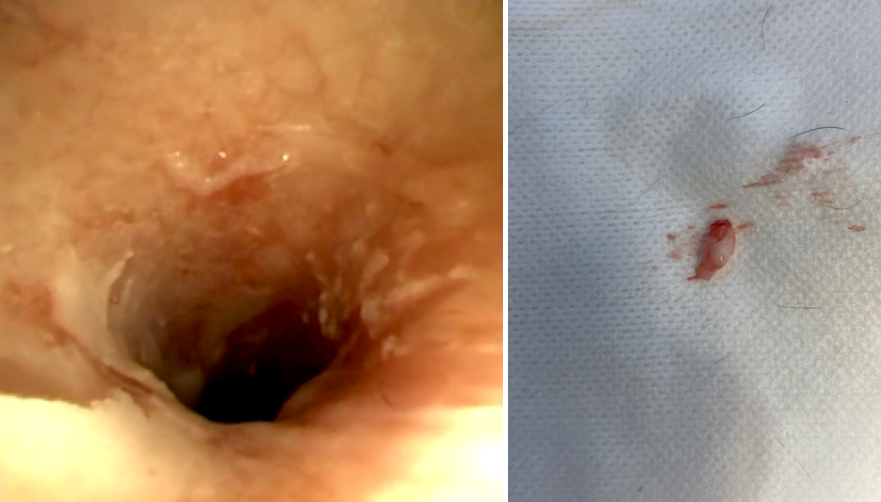

[내시경을 통한 이도 내 폴립 제거 후]

깨끗하게 제거된 이후 외이도의 상태 및 제거된 신생물(이도 내 폴립) 입니다.

처음에 비해 이도 내강이 확보되었으며, 내시경을 통해 외이전체를 플러싱 해줄 수 있었습니다.

경기동물의료원 (처인구동물병원)에서의 성공적인 고양이 귀 내시경 시술 이후, 내원 당시보다 호전된 증상을 보이며 외이의 삼출물 및 귀지의 감소를 확인할 수 있었습니다.

[수술 후 조직검사 결과]

조직검사 상에서 염증성 폴립으로 확인되어, 추가적인 절제나 수술 없이 관리할 수 있었습니다.